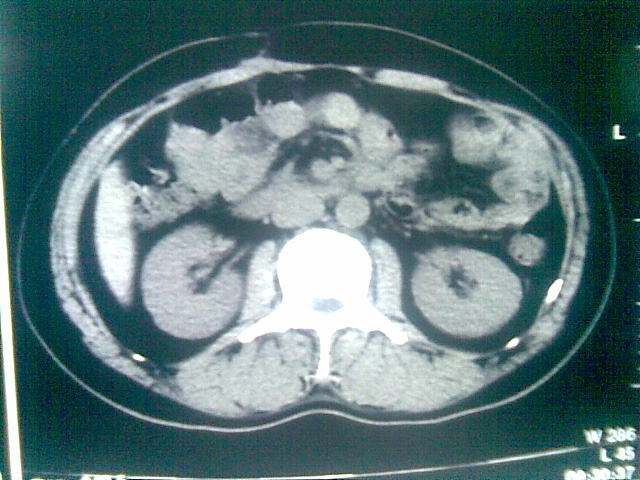

标题: CT23981:男,38岁阑尾炎术后透视胸腔积夜!做CT如下!积液包 [打印本页]

标题: CT23981:男,38岁阑尾炎术后透视胸腔积夜!做CT如下!积液包

可能与阑尾术后关系不太大,1.胸膜增厚粘连见少量气体。包裹脓气胸?左侧网膜囊脓肿?

少量积液部分粘连

左侧胸膜增厚、粘连+包裹液气胸。